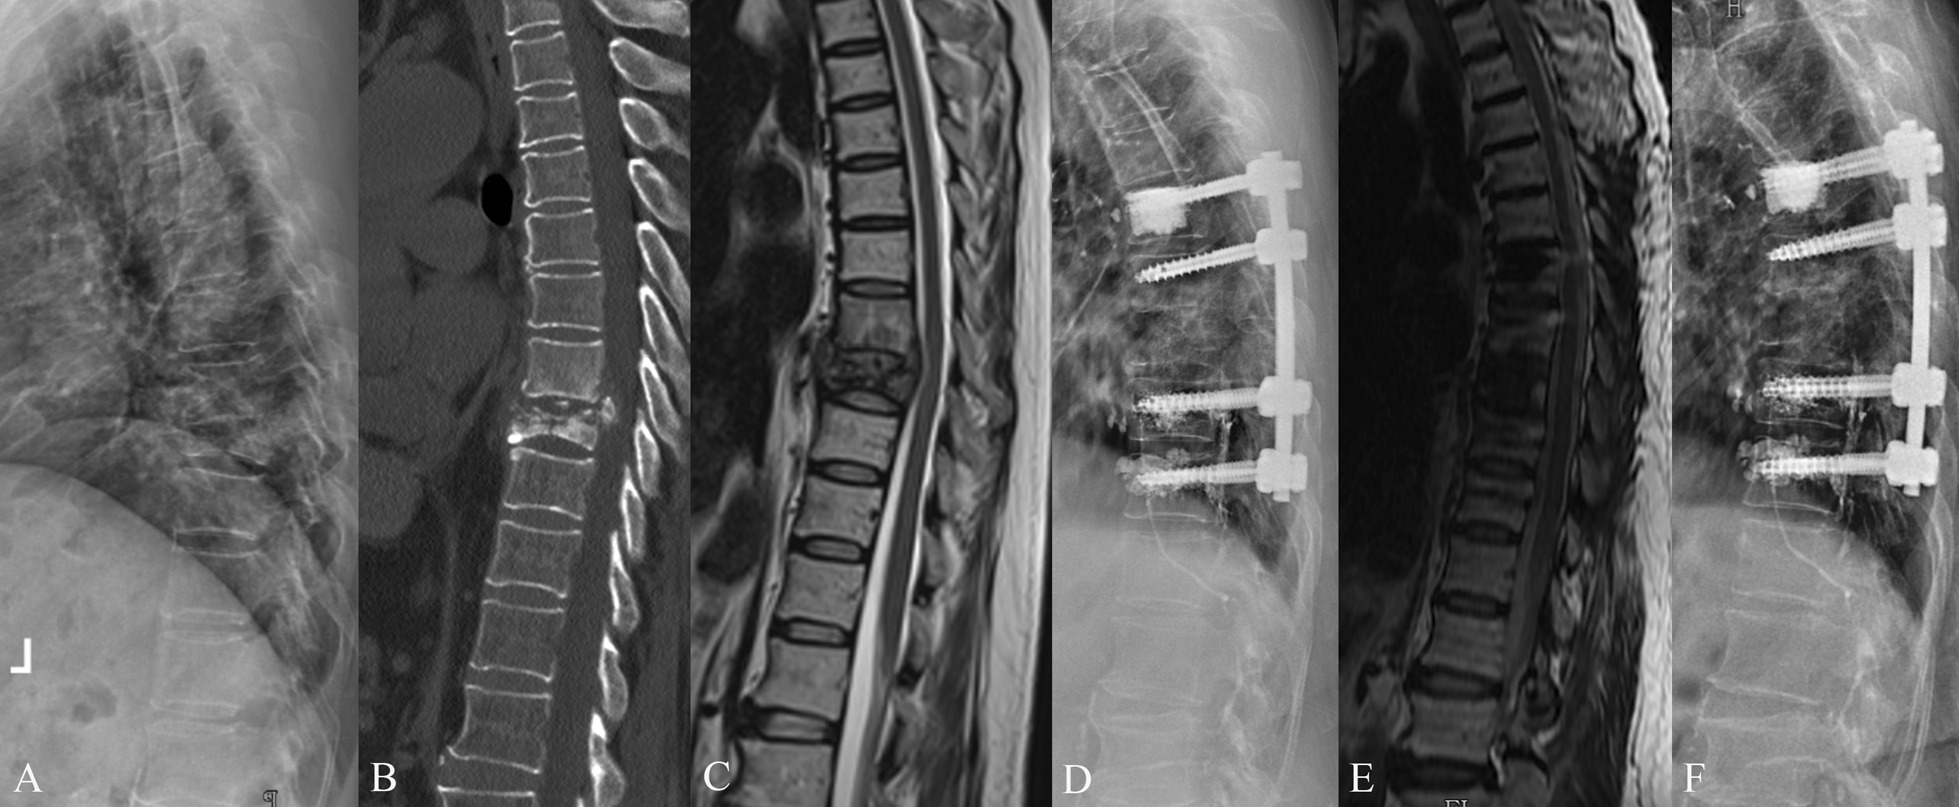

Fig. 2.

A 72-year-old female with L3-4 tuberculosis and severe osteoporosis. The patient underwent one stage posterior debridement, bone grafting, and fixation with cement-augmented pedicle screws. A–C Preoperative lateral X-ray, sagittal CT scan, and sagittal MRI scan images demonstrated bone destruction and intraspinal abscess. D Postoperative lateral X-ray image. E Sagittal CT scan at 8-month follow-up. F X-ray image at 25-month follow-up